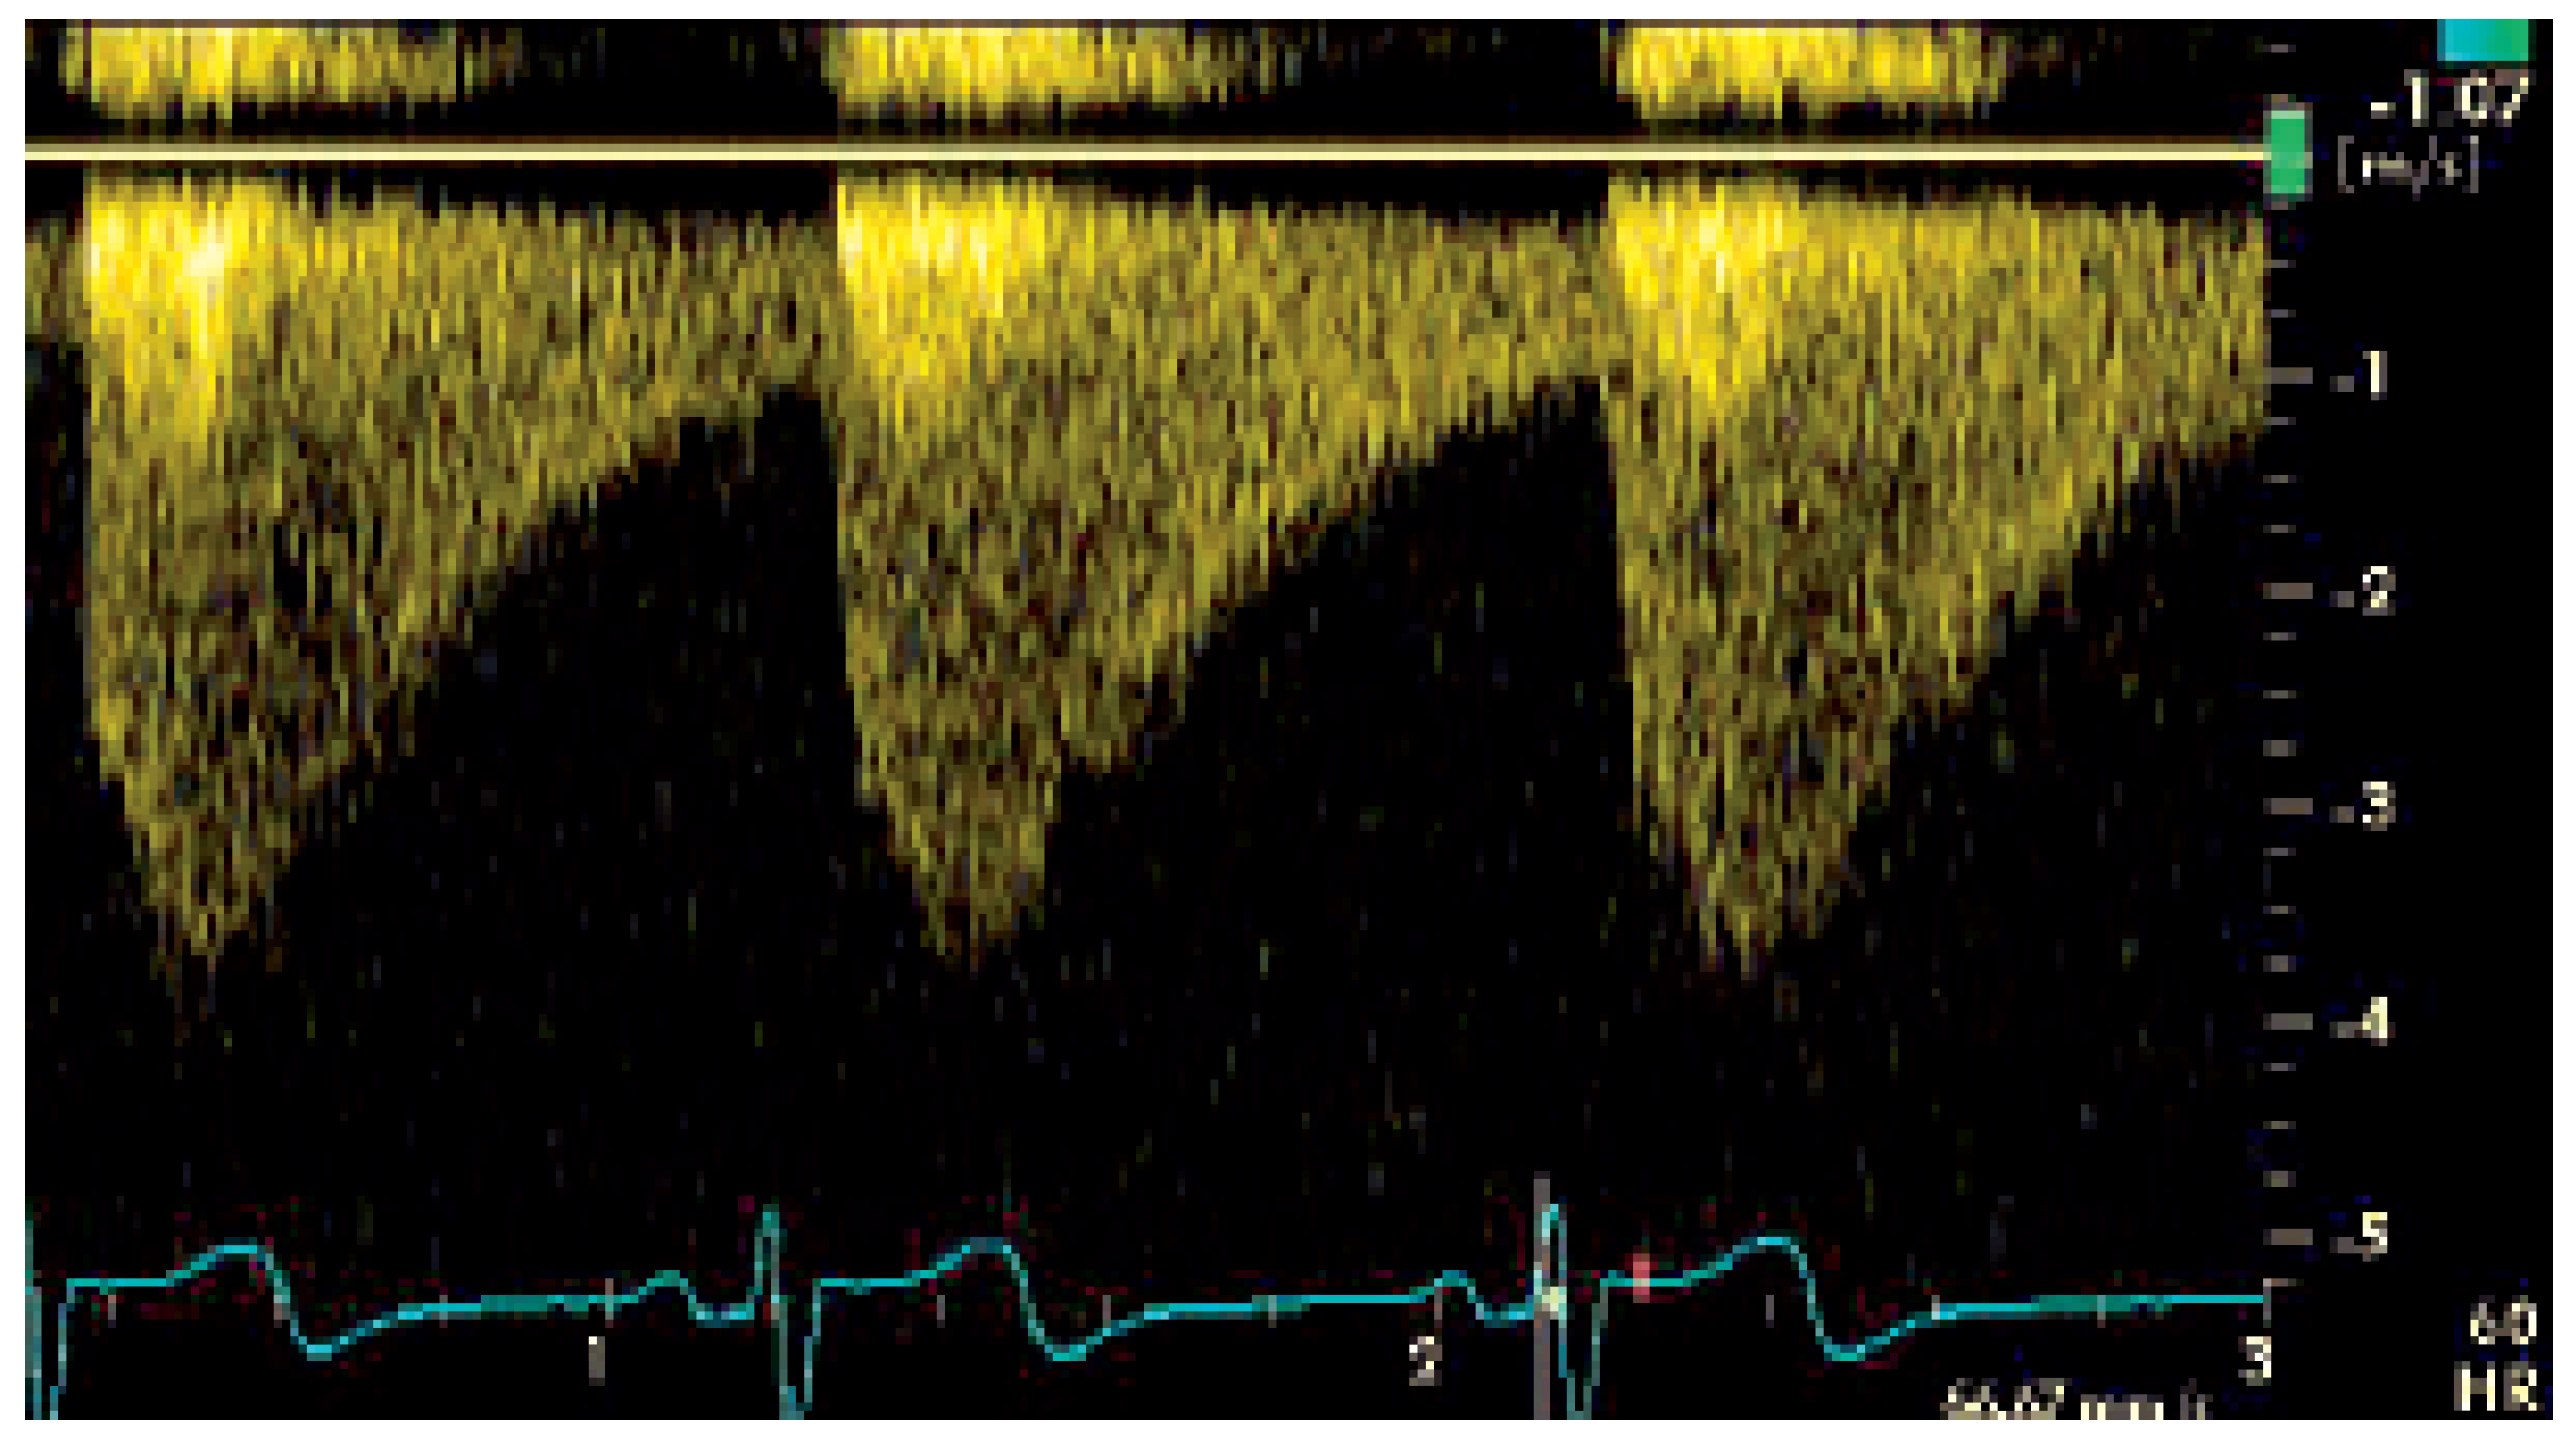

Figure 1.

Typisches systolodiastolisches Flussprofil, gemessen dopplersonographisch in der proximalen Aorta descendens nach der Stenose. Die maximale Flussgeschwindigkeit von 380 cm/sec entspricht einem Druckgradienten von max/mean 60/20 mm Hg.